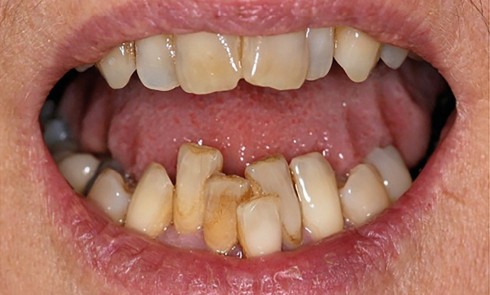

Article réservé à nos abonnés Préalables cliniques à la pose d’implant

L’implantologie fait actuellement partie des options de traitement prédictibles permettant de remplacer les dents manquantes, avec des taux de survie...

Le projet implantaire s’inscrit dans le plan de traitement global, qui comprend lui-même deux grandes phases de traitement : une phase...